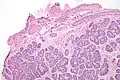

Micrograph of a Sertoli cell nodule. H&E stain. -

Sertoli cell nodules are unencapsulated nodules that consist of:[2][3][4]

- cells arranged in well-formed tubules (that vaguely resemble immature Sertoli cells), with

- bland hyperchromatic oval/round nuclei that are stratified, and

- may contain eosinophilic (hyaline) blob in lumen (centre).